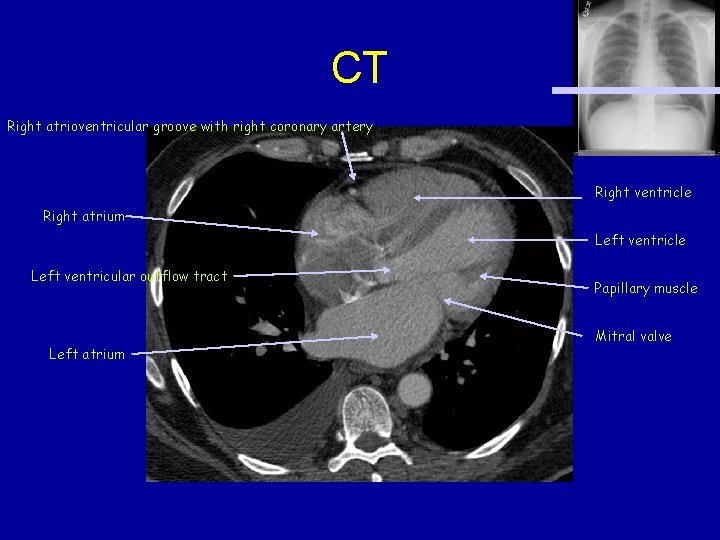

CT Right atrioventricular groove with right coronary artery Right ventricle Right atrium Left ventricle Left ventricular outflow tract Left atrium Papillary muscle Mitral valve